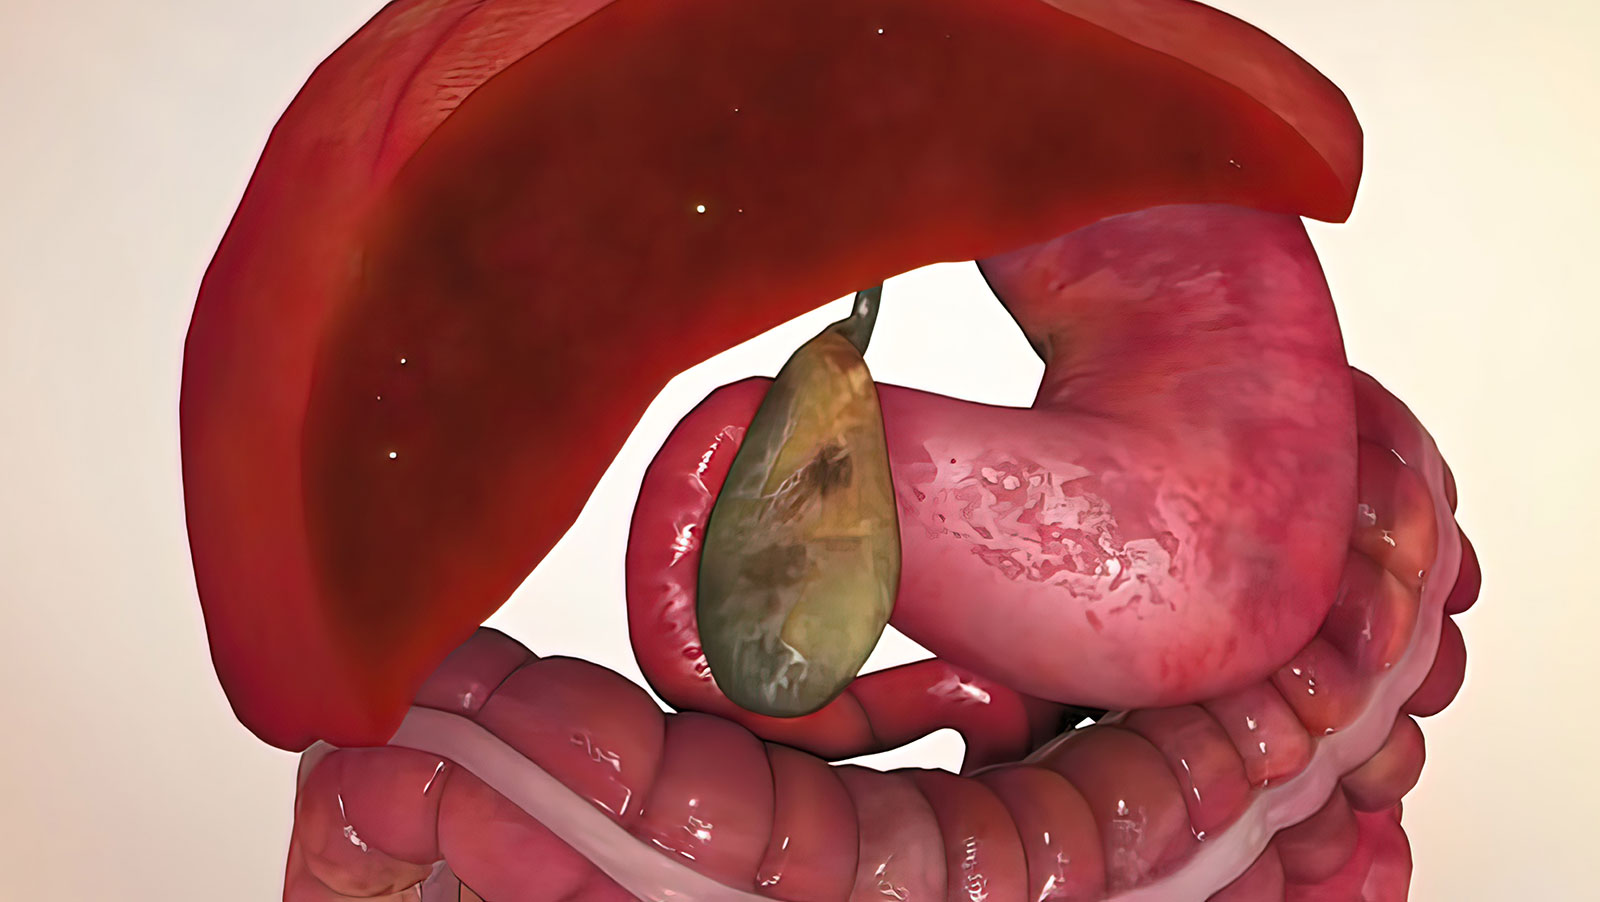

胆嚢は肝臓の下にある洋梨の形をした器官で、肝臓が生成する胆汁を貯蔵し、濃縮します。胆嚢は胆汁を小腸に放出し、脂肪を消化します。胆嚢摘出術は、米国で最も行われている手術の 1 つです。

胆嚢は、肝臓からの胆汁を貯蔵する洋梨の形をした臓器です。胆嚢は消化を助けるために胆汁を小腸に放出します。胆嚢は腹部の右側、肝臓の下にあります。

胆嚢は、腹部の右上、肝臓の下にある小さな臓器です。胆汁を貯蔵して放出し、消化器系による脂肪の分解を助けます。胆嚢の問題には、胆石、胆嚢炎、ポリープ、破裂、癌などが含まれます。